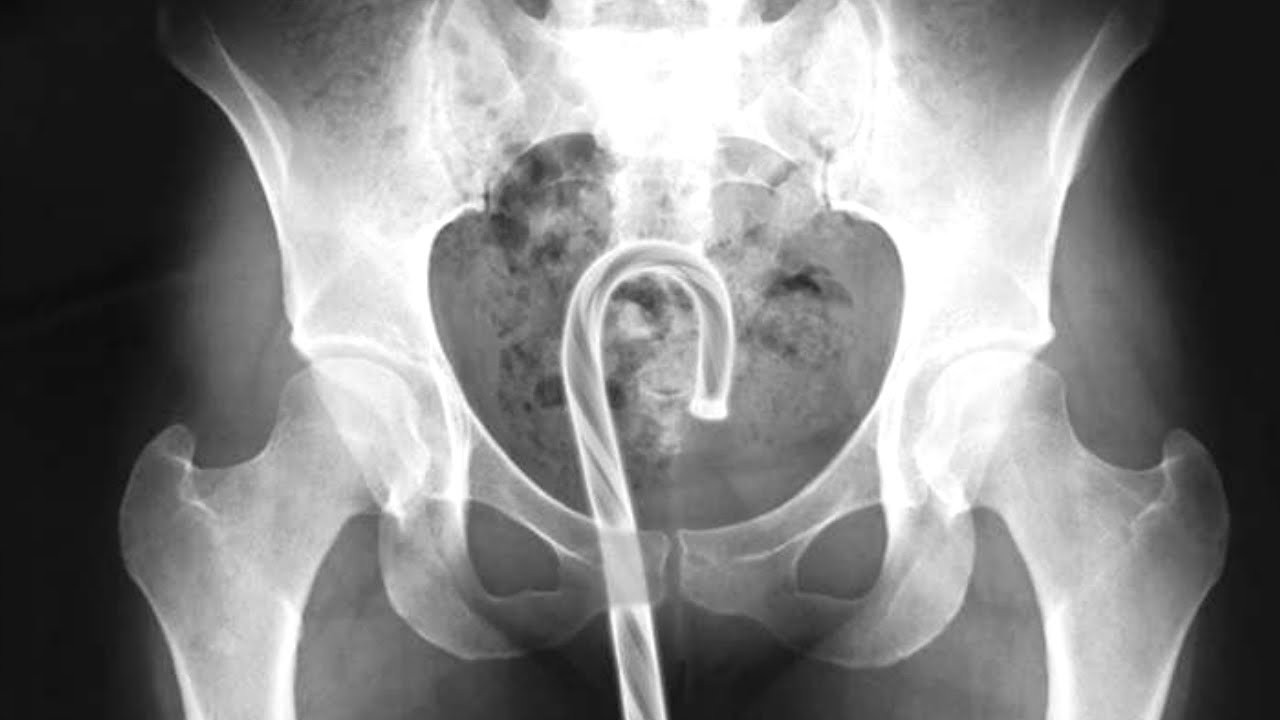

This is the time of year to be grateful for not having things stuck in our asses, and to think of those less fortunate than us. So spare a thought for those Americans who misjudged the capacity of their own orifices. All reports are taken from the U.S. Consumer Product Safety Commission’s database of emergency room visits,…